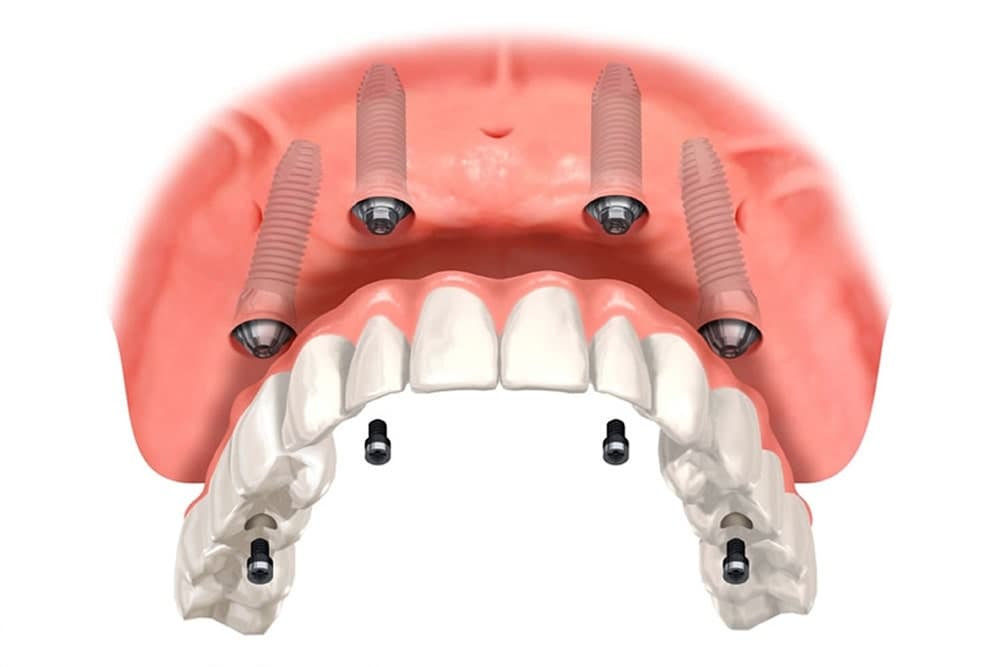

オールオン4

オールオン4とは、埋入した4本のインプラントで片顎全ての歯を支える方法です。一つひとつ個別にインプラントを埋入する方法に比べ、費用や外科処置の回数を軽減することができます。手術当日に仮歯を装着可能なため、見た目や咬み合わせについても即日で回復することができます。